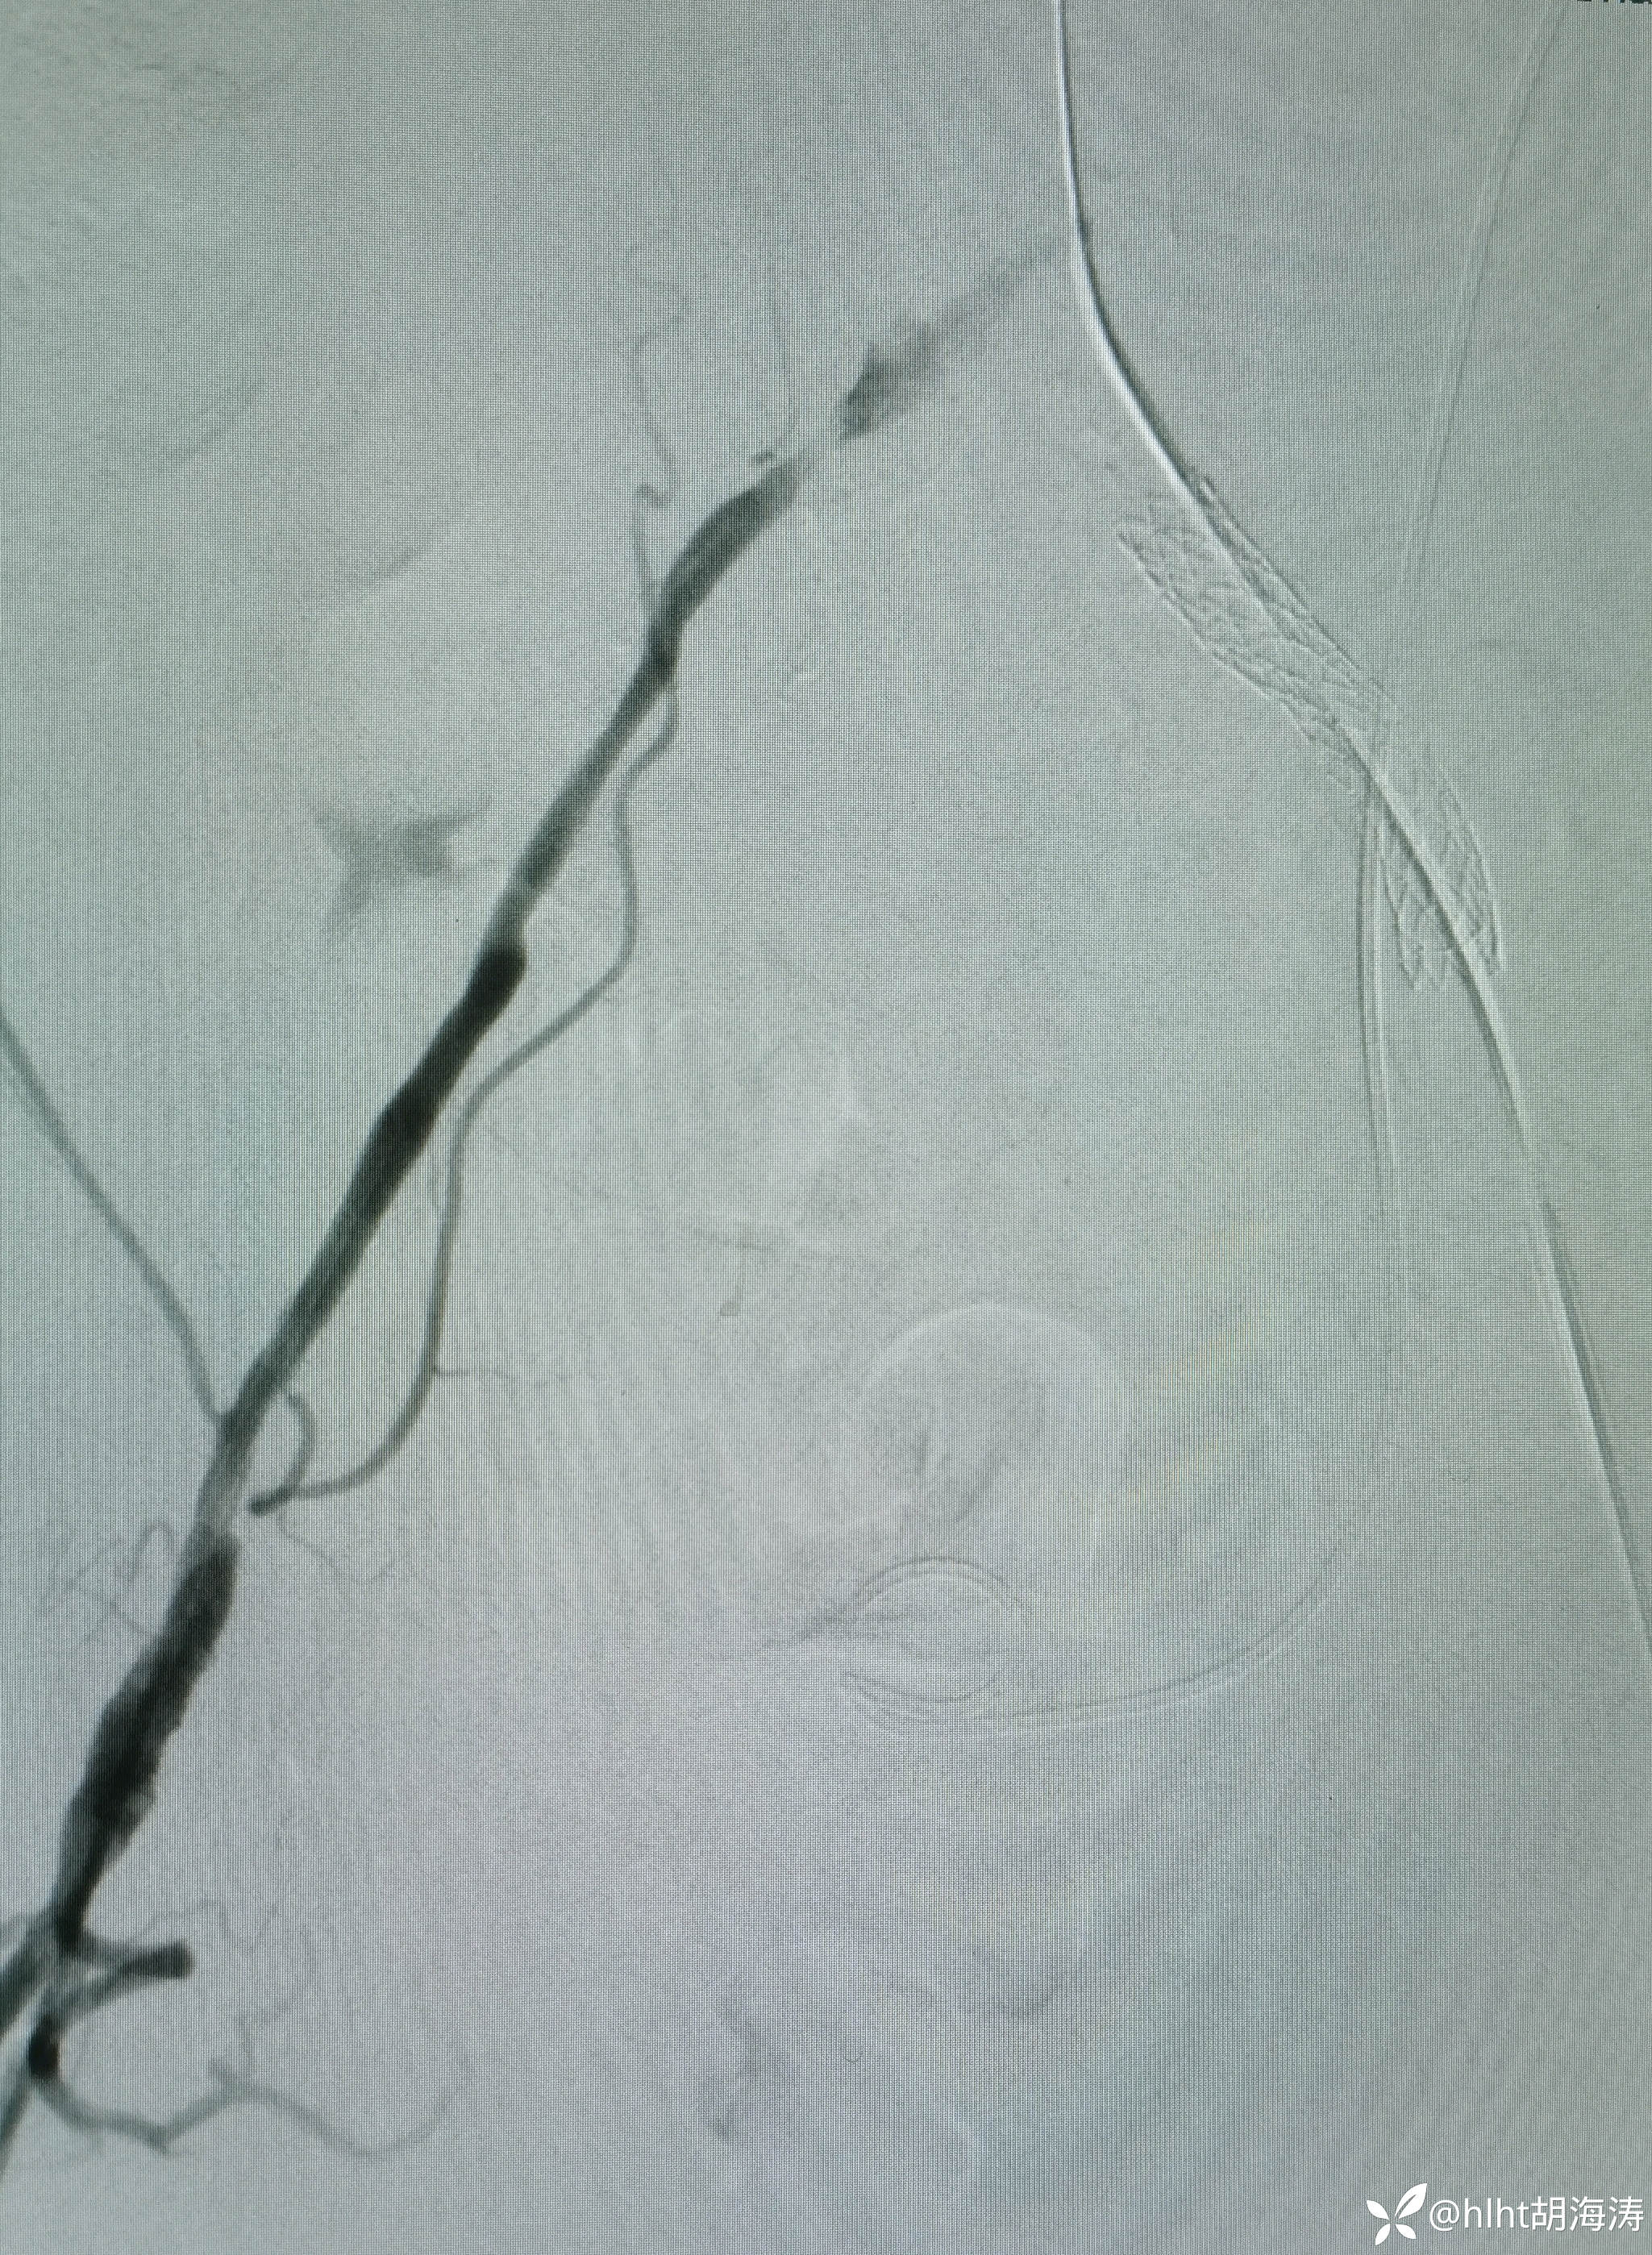

手术结束时,左侧下肢远端造影,很通畅:

23:00手术结束,双侧腹股沟区股动脉恢复搏动,右侧股浅闭塞段没法打通,侧枝循环好,手术顺利;

手术结束前,我再次造影看了双侧股浅动脉,血流好,没有血栓形成;